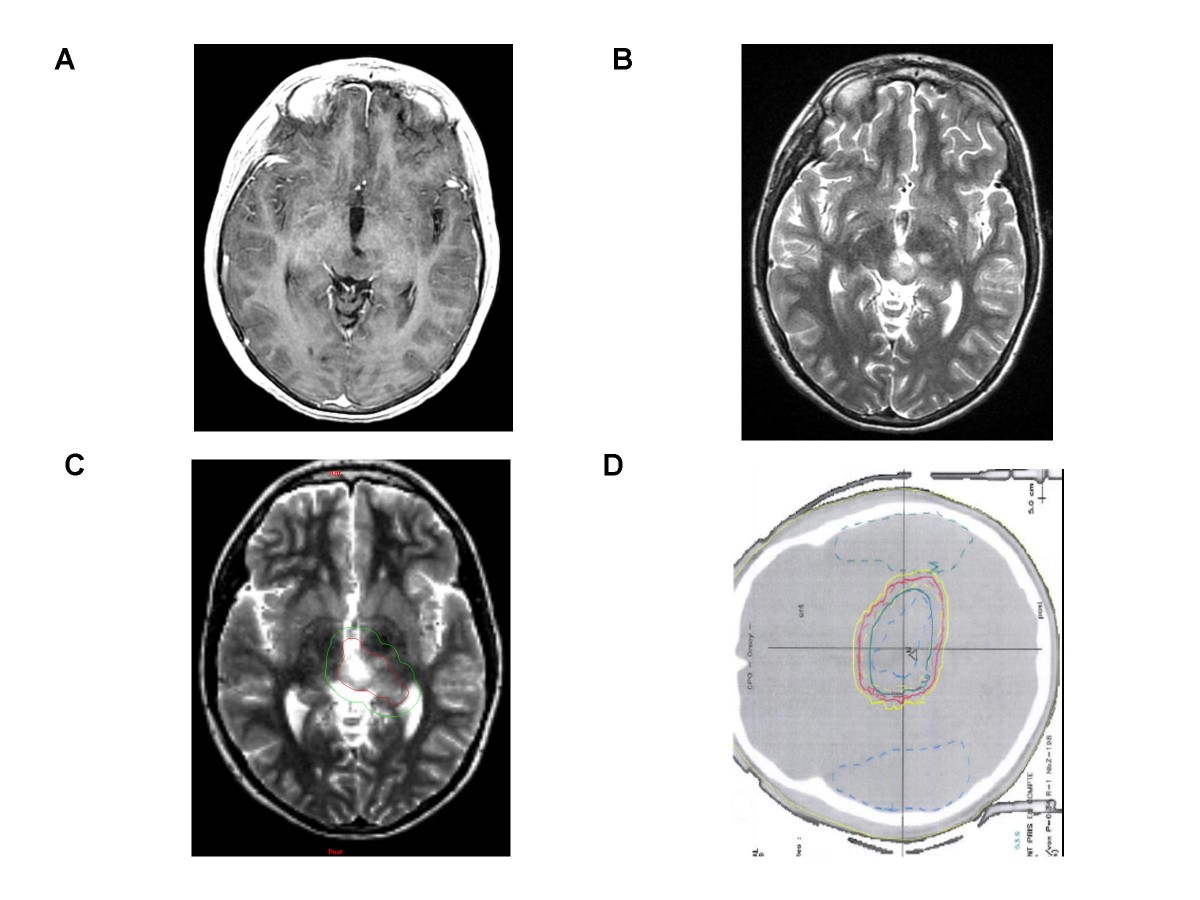

Figure 1. Conventional MR imaging, Target volume and Dosimetry of a Low-grade Glioma.

A left thalamic low-grade oligodendroglioma in a 10 year-old boy after partial resection, without contrast enhancement. [A] T1-weighted transaxial MR image after administration of intravenous Gd-DTPA [B] T2 -weighted sequence which shows ill-defined nodular images. [C] Representation of Gross tumor volume (in red) and Clinical target volume (in green). [D] Radiation field encompassing medial part of the left thalamus.

A healthy ten year-old boy with tinnitus and bilateral papillary oedema underwent a brain MRI showing a small tumour of the tectal plate. The lesion presented a signal of low intensity on T1-weighted and a high signal on T2-weighted sequences. No contrast enhancement was visible. The process was responsible for triventricular hydrocephalus by aqueduct compression. The first treatment was a ventriculocysternostomy followed, fifteen months later, by a partial resection when the lesion increased in size. Histopathological diagnosis was a grade II oligodendroglioma (WHO classification), with a proliferation index (MIB 1) of 5%. Three years after the first surgery, a systematic follow-up MRI revealed a recurrence localized on the quadrigeminal plate, close to the left thalami and the third ventricle, again without gadolinium enhancement. A second surgery was attempted, showing the same histology, but a tumour residue was left on the left thalamus (Figure 1). Treatment was completed six weeks later by RT using proton beams, delivering 54 Gy in 30 fractions of 1.8 Gy. Radiation fields encompassed the medial parts of the thalami (Figure 1C, D). Radiological and clinical data were then evaluated every 3 months thereafter. Six months after RT, systematic MRI found obvious development of a new lesion with an important contrast enhancement and mass effect on the third ventricle (Figure 2), however the patient remained asymptomatic.